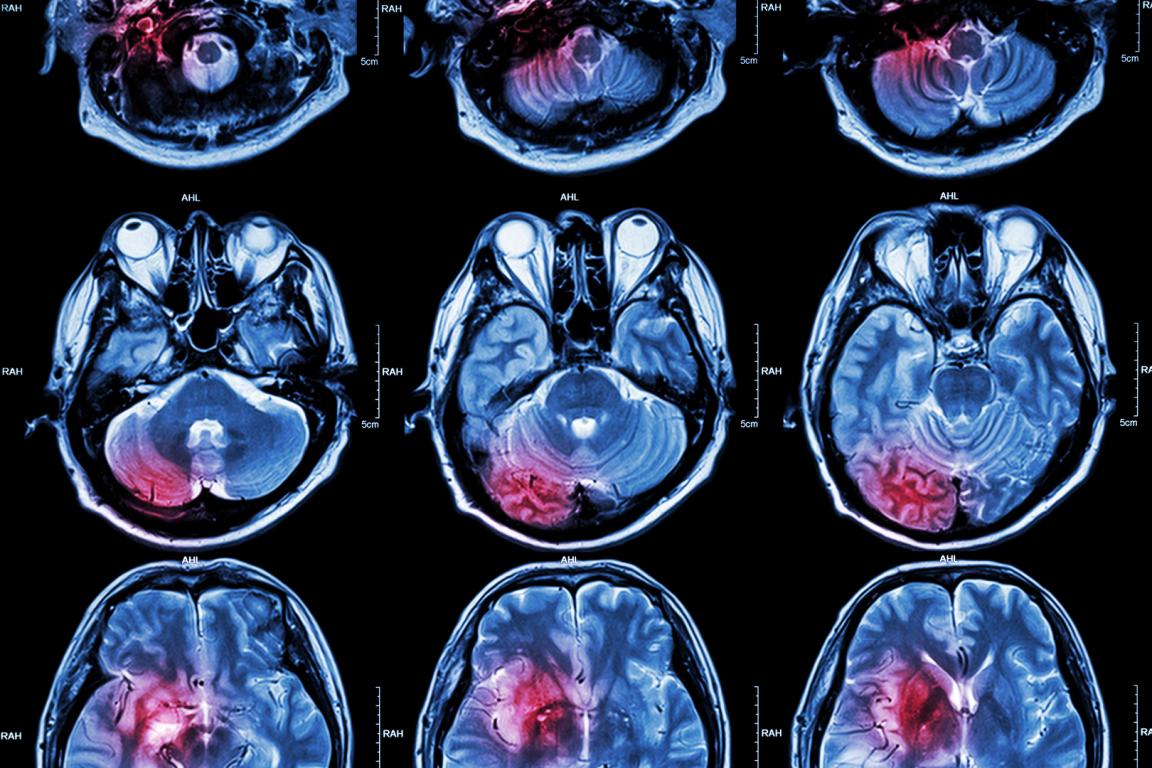

Hemangioblastomen zijn het prototype tumoren bij patiënten met de ziekte van Von Hippel-Lindau (VHL). Deze ziekte kent echter meer manifestaties met een maligne potentie. VHL kent een hoge morbiditeit, vooral als de symptomen van de tumoren laat onderkend worden. In het bijzonder dragen de hemangioblastomen bij aan een hoge ziektelast en slechte prognose. Een multidisciplinaire benadering met gerichte expertise zijn een voorwaarde voor goede zorg. Hierin zijn de neuroloog en neurochirurg erg belangrijk. De laatste jaren zijn er baanbrekende ontwikkelingen geweest zoals de kennis over het HIF (hypoxia induced factor)-eiwit en het eerste geneesmiddel dat hier direct op aangrijpt. Dit geeft hoop op betere overleving en minder ziektelast. Dit artikel gaat in op de moleculaire achtergrond, de klinische symptomen en nieuwe perspectieven voor patiënten met VHL.